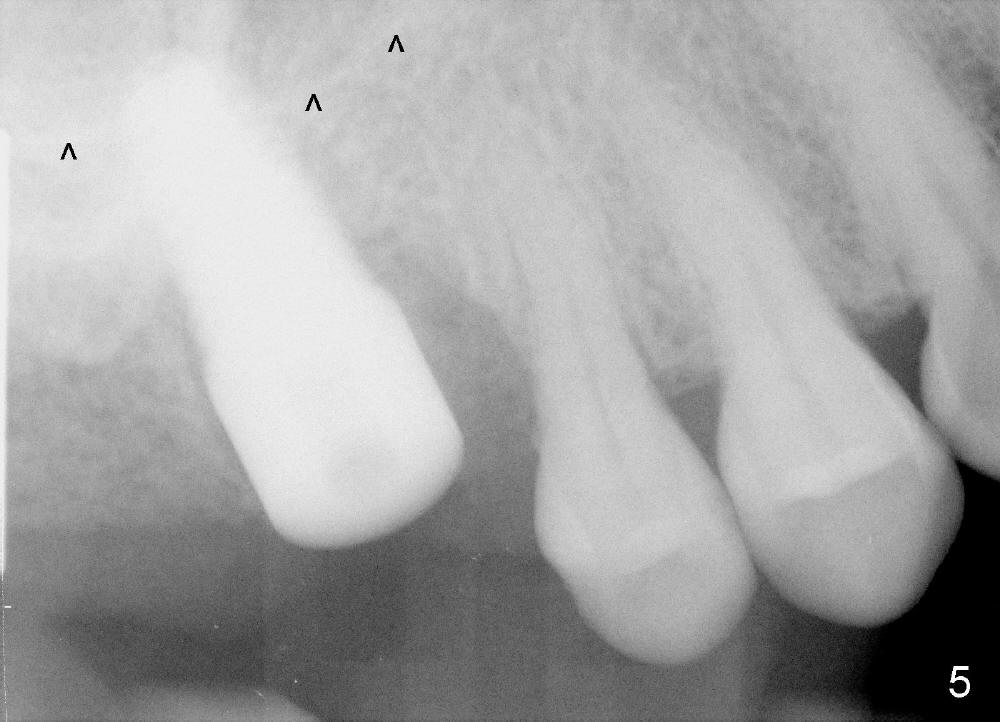

The upper right 1st molar fractures, the lingual portion mobile (Fig.1). There are deep pockets mesiolingually and distolingually. Fig.2 is preop PA, showing mesial bone resorption (*). The 84-year-old lady agrees extraction and immediate implant. Extraction is difficult due to not only root fracture but also hemorrhage. Following debridement of granulation tissue, the 3 sockets are packed with gauze for hemostasis. Even so, there is oozing from the bone. The septum can not be seen clearly. Its position is determined by an explorer. Osteotomes have to be used for osteotomy in the septum, followed by taps. The first intraop PA shows that 5x20 mm tap penetrates the sinus floor (Fig.3 ^). The osteotomy is further enlarged until 7x17 mm tap with stability (Fig.4). So far there has been no sign of sinus membrane perforation. Mixture of freeze dry mineralized bone and Osteogen is placed in the socket and pushed to the buccal and lingual walls as well as into sinus using a 4 mm flat end osteotome. A 7x17 mm implant is initially difficult to be inserted possibly due to blockage by bone graft. The osteotomy have to be recreated by a series of osteotomes and taps before placement of the 7x17 mm implant. It appears that the apical threads have been engaged into the sinus floor for primary stability (Fig.5). The insertion torque is 40 Ncm. According to our experience (1,2), this is not enough; finally the torque is increased to 60 Ncm by turning the implant more apically. The large implant obliterates the socket mesiodistally; the buccal and lingual gaps are filled with bone graft, followed by a collagen membrane (Fig.6 *) and suture. In order to protect the membrane, a short abutment is placed (A) and perio dressing (Fig.7*) is placed without occlusal interference. The abutment is removed 1 month postop, as the perio dressing has been dislodged. The patient returns for restoration 8 month postop. Bone regeneration occurs apparently in the coronal aspect of the implant (Fig.8), especially mesially (*, as compared to Fig.5). The gingiva-level implant is slightly subgingival mesially (Fig.9 M), probably due to high placement (compare to Fig.6). There is no bone resorption 6 months post crown (Fig.10 C) cementation.